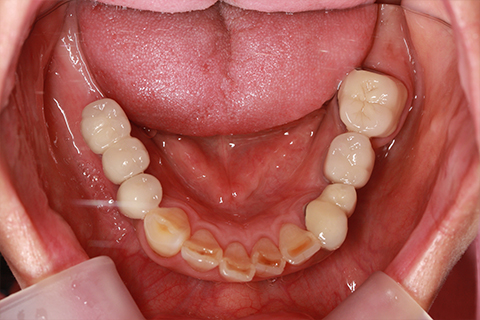

治療後

- 年齢・性別

- 57歳男性

- 治療期間

- 3ヶ月

- 抜歯

- なし

- 治療費

- 154万円

- 備考

- 左上5.6.7 及び左下6.7欠損

- 治療内容

- 左上5.6.7と左下6.7欠損部にインプラント埋入

- 施術の副作用(リスク)

- オペによる知覚障害。インプラントによる歯肉炎。インプラント脱落。